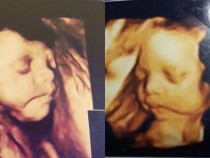

배우 홍지민이 두 딸의 초음파 사진을 공개해 눈길을 끌었다.최근 그는 자신의 인스타그램에 "로시와 그레이스의 입체 초음파 ~~~~그레이스를 만나기 5일전 두둥 그레이스는 과연 어떤 모습일까? 설레고 설레고 또 한편으로는 너무 아플까봐 살짝 무섭기도 하고 ㅋㅋㅋ으~~~~..